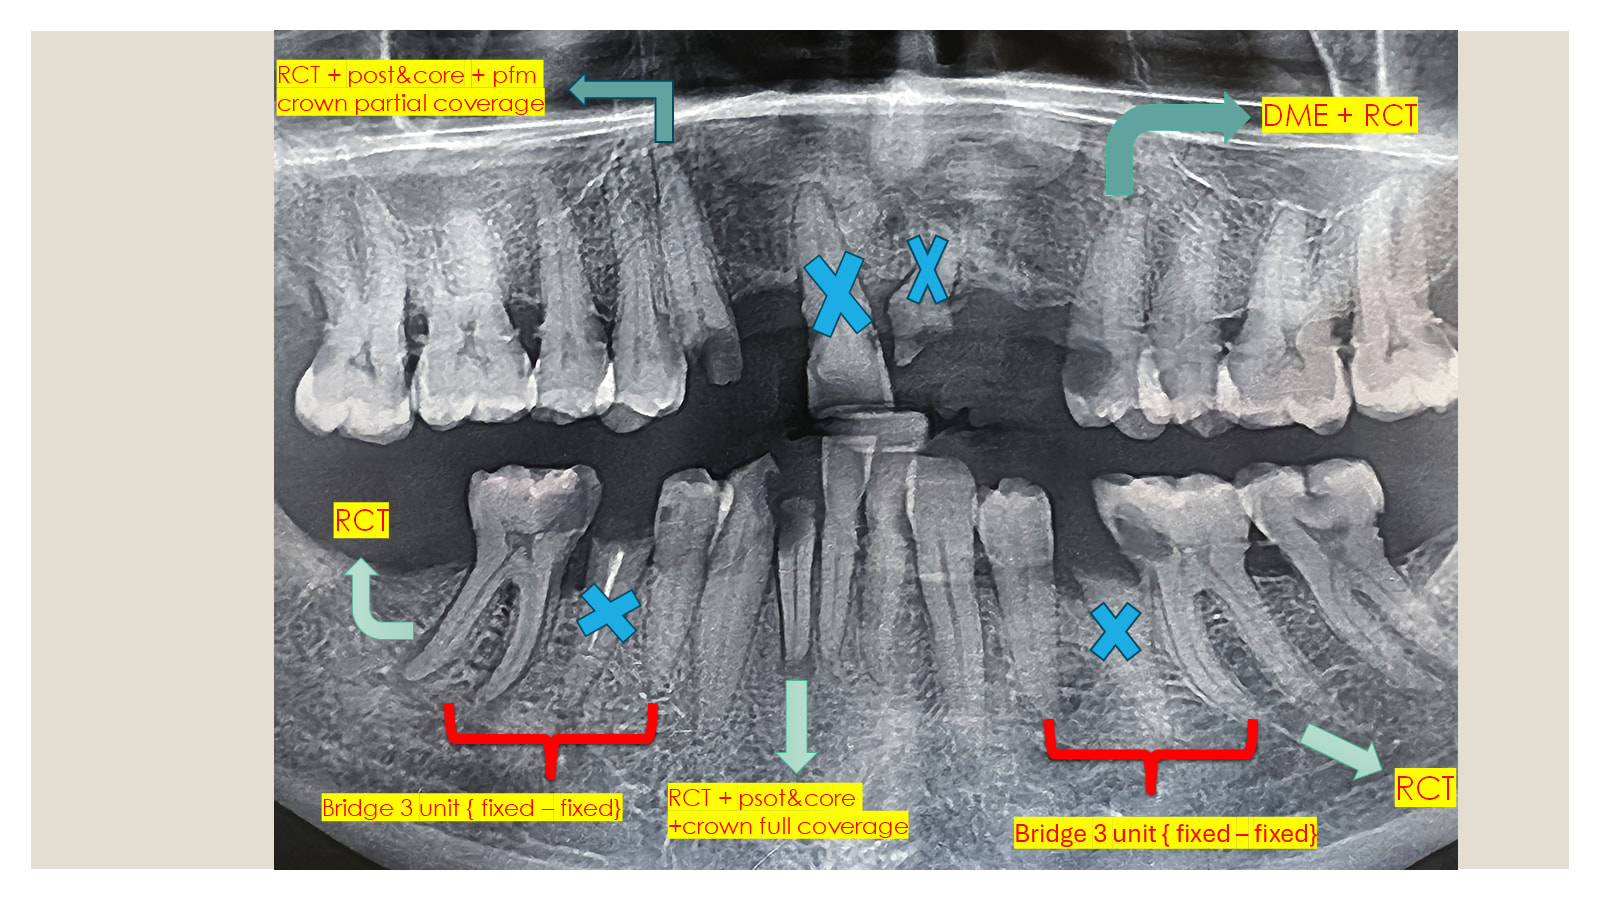

يسرنا أن نسلّط الضوء على جهود طلاب الفرقة الخامسة خلال أدائهم الإكلينيكي المتميز، حيث يجسّدون مزيجًا من العلم، المهارة، والالتزام.

هذه اللقطات توثق خطوات ثابتة نحو التخرج والريادة في مجال طب الأسنان، وتعكس روح المسؤولية والتفاني في تقديم أفضل رعاية للمرضى تحت إشراف نخبة من أعضاء هيئة التدريس.